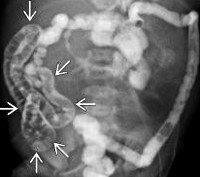

При пальпации живота выявляется болезненность и напряженность передней брюшной стенки, чаще несимметричная, более выраженная справа. Заметно вздутие живота и увеличение его размеров в верхней части, в нижних отделах при этом обычно обнаруживается западение. Пальпировать петли кишечника в нижней части живота нередко не удается. На рентгенограмме - типичные признаки острой кишечной непроходимости: симптом двойного газового пузыря (в желудке и 12-перстной кишке) и расширенные петли кишечника. Рентгенография с контрастированием четко показывает расширенный желудок и верхнюю часть тонкой кишки, что тоже является признаком обструкции при незавершенном повороте кишечника.

Ирригография указывает на нетипичное расположение слепой кишки в правом верхнем квадранте брюшной полости, что и является причиной непроходимости, поскольку именно тяжи брыжейки слепой кишки механически сдавливают просвет 12-перстной кишки. Новорожденным также проводится УЗИ-исследование, с помощью которого можно увидеть косвенные признаки незавершенного поворота кишечника. В частности, определяется аномальное расположение верхней брыжеечной вены по отношению к одноименной артерии. Кроме того, нижние отделы 12-перстной кишки локализуются с правой стороны, что также характерно для данного порока развития.